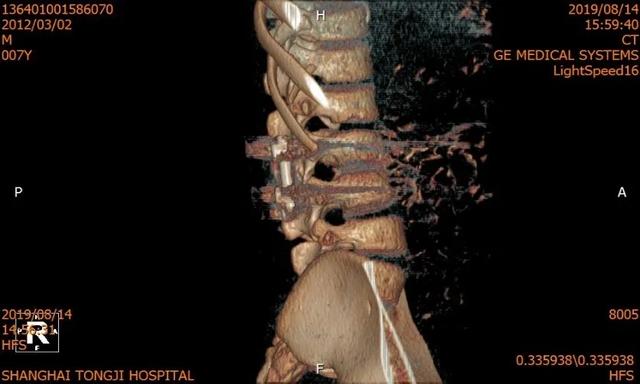

医疗团队本着对少年儿童的关爱,把担子压在自己肩上,准备得仔细又仔细。术前还以患者畸形脊柱的超薄 CT 为基础,运用最先进的 3D 打印技术构建了患者脊柱模型,并利用数字模拟技术模拟了患者内固定的最佳植入路径,反复模拟手术,做好了充分的术前准备。

术前 CT & 3D 打印

术后 CT